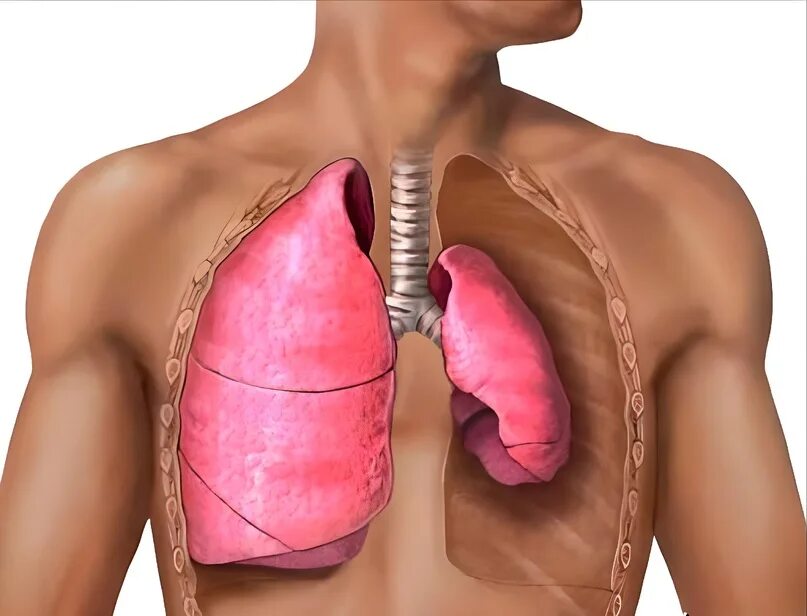

Коллабированное легкое при пневмотораксе